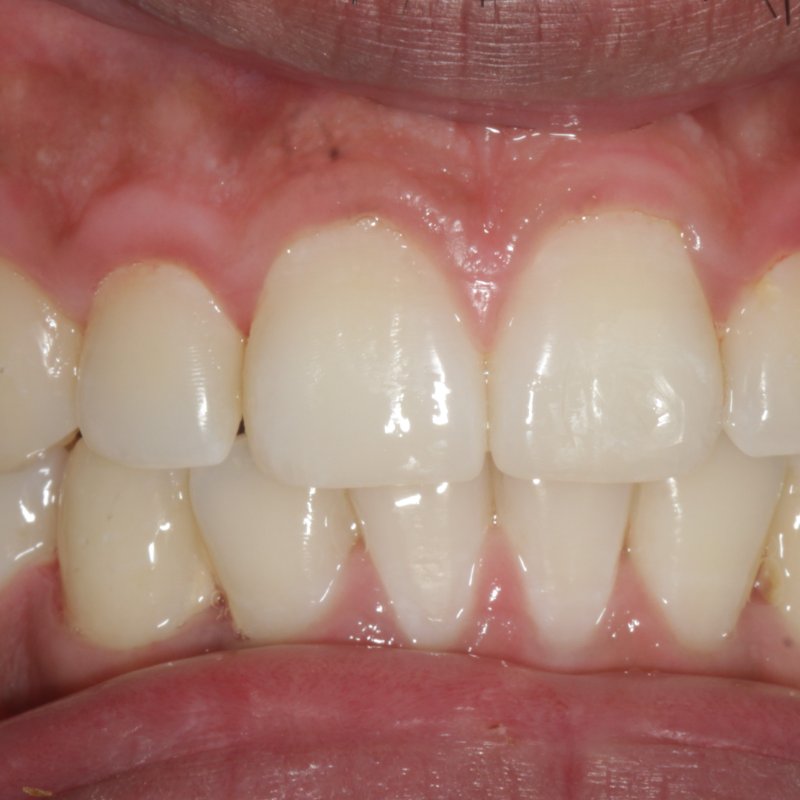

After smile makeover

Smile Makeover

Crown & veneer restoration

Stained, worn dentition restored to a clean, confident smile with porcelain crowns and a refreshed gum line.